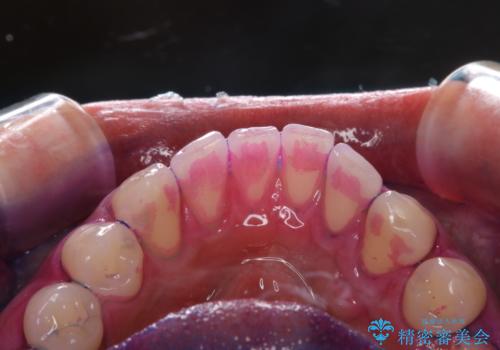

親知らずを抜いて1週間後にPMTC 歯のクリーニング

- 親知らずの抜歯後の約1週間後に抜糸(縫った部分の糸とり)で来院されました。その際、抜歯後は傷口が怖くて歯磨きが上手くできず、汚れや口臭が気になるためクリーニングも希望されました。

抜歯後は多少出血したり、違和感や痛みを感じたりすることがあります。そのため親知らずを抜いたり、外科的な処置をするといつも通りの歯磨きがしづらくなります。また、傷口の周りが心配で、歯ブラシをするのが怖くなるものです。抜歯後落ち着いたら、歯科医院にて専門の機械を使用しクリーニングをすることがおすすめです。抜歯前や後にPMTCを行うことで、お口の中の健康維持につながり、その後の感染・腫れ・口臭予防などになります。

親知らず抜歯後正常に治癒が進んでいれば1週間後から可能です。